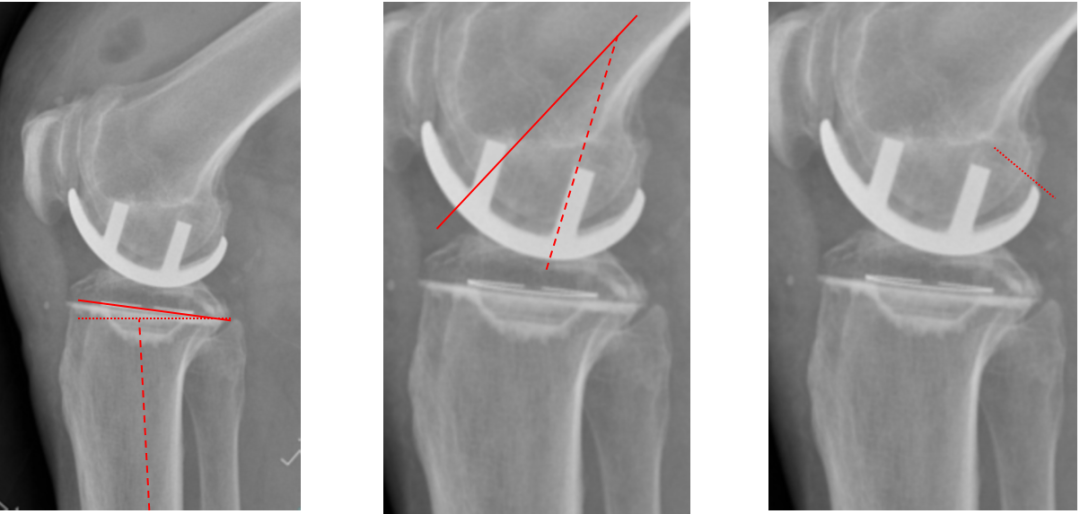

胫骨假体3°内翻

AP位胫骨与股骨假体位置:胫骨假体内翻3°,股骨假体中轴线与胫骨假体垂直。

胫骨假体厚度合适

胫骨垫片厚度合适:术前内翻畸形基本矫正,残留2-3°内翻。

胫骨假体内侧悬挂

AP位胫骨假体位置:胫骨假体内侧悬挂>2mm。

股骨假体偏内放置

AP位胫骨与股骨假体位置:股骨假体轻度内翻,中轴线与胫骨假体中线不一致,偏内侧。

胫骨假体偏大,且后倾不足

侧位胫骨假体位置:胫骨假体后侧悬挂>2mm,后倾2°。

胫骨假体后倾角度大

侧位片胫骨假体位置:胫骨假体后倾12°,前后缘齐平 。

股骨假体偏小

侧位片股骨假体位置:股骨假体偏小,与胫骨假体后缘不齐平;屈曲15°,未包容股骨后髁。

股骨假体偏大

侧位片股骨假体位置:股骨假体与胫骨假体不匹配,股骨假体大一个型号,屈曲45°,后缘空虚。

股骨假体屈曲角度大

侧位片股骨假体位置:股骨假体与胫骨假体匹配,股骨假体屈曲62°,前缘翘起。